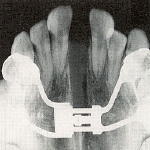

拡大前X線像

拡大前X線像 拡大直後のX線像

拡大直後のX線像 拡大後半年後のX線像

拡大後半年後のX線像

X線像

1か月で6mmほど拡大したため、急速な拡大に骨の新生が追いつかないため、拡大直後の正中縫合はまだ骨が出来ていません。そのためX線像では正中部が透過像となり黒く抜けていることが分かります。その後、約半年かけて、正中部に新しい骨が出来ると、新しい癒合部が出来ます。つまりその分だけ、上顎骨の横幅が拡大したことになります。